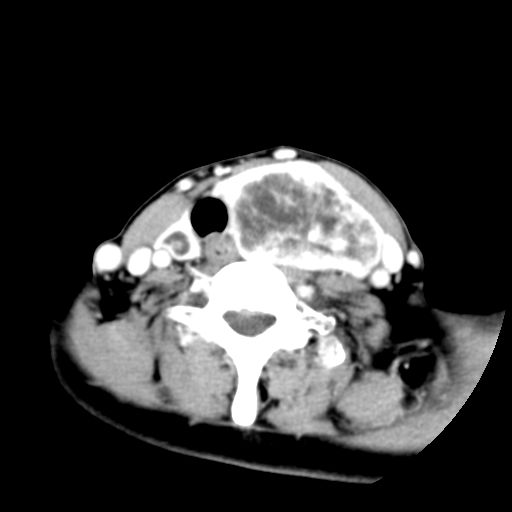

女  53岁  左侧甲状腺肿物3年,近2月明显增大。病理稍后发。

左侧甲状腺内见有一较大类圆形低密度区,边缘清楚光整,增强有一定强化,但仍较正常甲状腺组织强化弱,左侧甲状腺周围组织明显受压移位,且周围组织界限存在,周围组织间隙内未见肿大淋巴结,结合病史考虑为良性病变,左侧甲状腺腺瘤可能大。

右侧也有一个低密度灶,甲状腺ct定性不是强项,我考虑为甲状腺的良性病变。

双侧都有,最大病灶在左侧,其包膜和灶内部都有明显的强化,提示其血供丰富。我首先考虑是良性占位,以腺瘤可能性大。

左侧甲状腺内见有一类圆形低密度区,边缘清楚光整,可见明显增强,间隔亦可见增强,且与周围组织分解清晰,周围组织间隙内未见肿大淋巴结。右侧亦可见类似表现。考虑甲状腺腺瘤。

手术病理证实:双侧腺瘤样甲状腺肿。